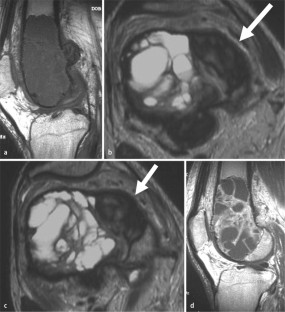

MRI morphology of bone tumors and tumor-like lesions

Für das Staging und die Charakterisierung von Knochentumoren und tumorähnlichen Läsionen ist in der Magnetresonanztomographie (MRT) der Einsatz von Spinechosequenzen erforderlich. Die MRT hat nur einen geringen Stellenwert in der Bestimmung der Dignität. Obwohl viele Knochentumoren und tumorähnliche Läsionen eine vergleichbare Morphologie in dieser bildgebenden Modalität aufweisen, können einige Tumorentitäten mittels MRT recht zuverlässig diagnostiziert werden. Hierzu zählen Knorpeltumoren, die solitäre und aneurysmatische Knochenzyste, der Riesenzelltumor, fetthaltige Läsionen und bis zu einem gewissen Grad auch das Osteoidosteom und das Osteoblastom. Es werden praktische Tipps gegeben, wann bei Tumorverdacht die MRT eingesetzt werden sollte, wie bei einem zufällig bei einer MRT gefundenen Tumor die Untersuchung modifiziert werden sollte und welcher Tumor vorliegen könnte.

Spin-echo sequences are mandatory at MRI for staging and characterization of bone tumors and tumor-like lesions. MRI is of minor value in the estimation of the malignant potential of an osseous lesion. Although many bone tumors and tumor-like lesions present similar morphology at MRI, some entities can be diagnosed with good reliability. These include chondrogenic tumors, solitary and aneurysmal bone cysts, giant cell tumors, lesions containing fatty tissue and, to a certain extent, osteoid-osteomas and osteoblastomas. Practical advice is given regarding when to perform a MRI study in cases of tumor suspicion. Further advices are given for cases a tumor is found incidentally at a MRI study, how to modify the study and which kind of tumor may be present.